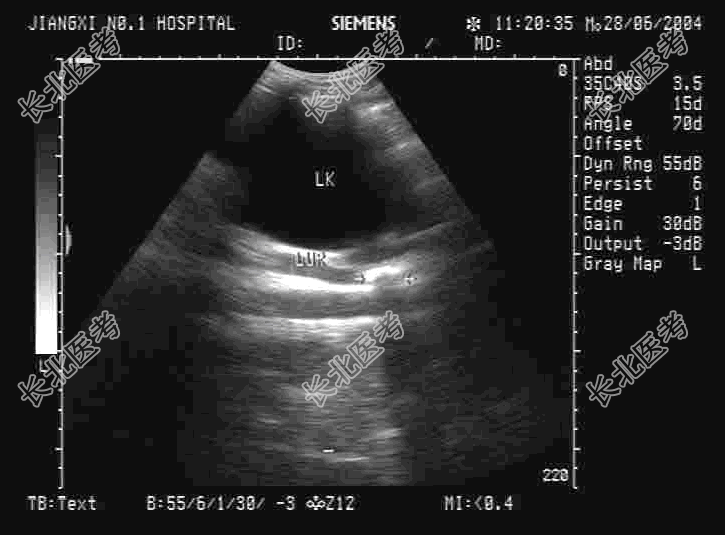

- 单项选择题某患者左腹部疼痛,根据左肾区超声检查如图, 以下最可能的诊断为

A、左输尿管结石并左肾轻度积水

B、左肾结石

C、左输尿管结石

D、左输尿管结石并左肾重度积水

E、左肾结石并左肾积水